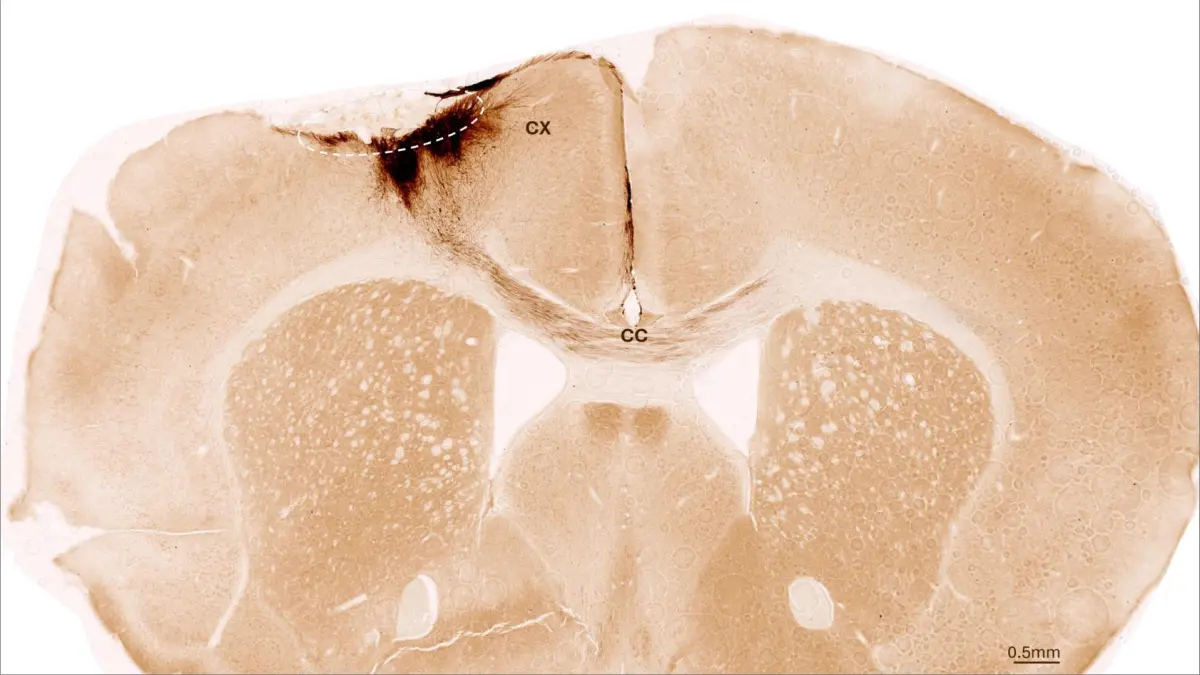

Stammzellen reparieren Mäusehirn nach Schlaganfall